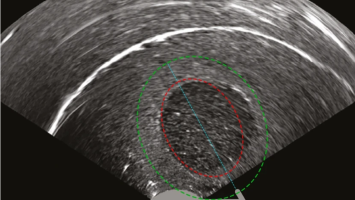

Worauf man bei der Sonografie von Adnexbefunden achten sollte

Die Abgrenzung zwischen benignen und malignen Veränderungen anhand des transvaginalen Ultraschalls wird hierzulande noch immer unterschätzt. Worauf Sie achten sollten und welche Schritte bei einem Befund zu unternehmen sind, lesen Sie hier.

Springer Medizin Podcast - Endometriose/© (M) Willer D. et al. / all rights reserved Springer Medizin Verlag GmbH Logo: Springer Medizin Verlag GmbH, Ärztin misst Blutdruck bei Schwangeren/© Andrey Popov / Stock.adobe.com (Symbolbild mit Fotomodell), Schwangere Frau hält Tablette und Glas Wasser/© NDABCREATIVITY / stock.adobe.com (Symbolbild mit Fotomodell), Justiz/© hawi_101 / Fotolia, CT des Uterus einer 47-Jährigen /© Rizos A et al. | all rights reserved Springer Medizin Verlag GmbH, Gardnerella spp. bedeckte Schlüsselzellen/© Swidsinski A et al. / all rights reserved Springer Medizin Verlag GmbH, Impfung/© Remains / Getty Images / iStock (Symbolbild mit Fotomodellen), Junge Frau sitzt auf Toilette/© Dragana Gordic / stock.adobe.com (Symbolbild mit Fotomodell), Spritze wird aufgezogen/© scyther5 / Getty Images / iStock, Ultraschall der "kissing ovaries" bei Endometriose/© Willer D. et al. / all rights reserved Springer Medizin Verlag GmbH, Ärztin führt Ultraschall bei einer Frau durch/© satyrenko / stock.adobe.com (Symbolbild mit Fotomodellen), Doxy-PEP/© Tobias Arhelger / stock.adobe.com, Junge Frau zur Beratung bei Ärztin/© demaerre / Getty Images / iStock (Symbolbild mit Fotomodellen), Schwangere macht Gymnastik/© fotostorm / Getty Images / iStock (Symbolbild mit Fotomodell), Junge Patientin im Gespräch mit einer Ärztin/© FatCamera / Getty Images / iStock (Symbolbild mit Fotomodellen), Urogenitale Fistel bei einer 36-jährigen Patientin/© Lautenschlager S et al. / exklusiv lizenziert an Springer-Verlag GmbH Austria, ein Teil von Springer Nature 2024, CT bei endometrioidem Karzinom/© Kuzinska MZ et al. / all rights reserved Springer Medizin Verlag GmbH, Frau nimmt Diaphragma in der Hand/© AndreyPopov / Getty Images / iStock (Symbolbild mit Fotomodellen), Ein Abstrich vom Gebärmutterhals wird auf ein Objektivträger geschmiert/© Tatiana Buzmakova / Getty Images / iStock (Symbolbild mit Fotomodellen), Frau nutzt Pen am Bauch/© bung / Stock.adobe.com (Symbolbild mit Fotomodell), Reife Eizelle im Mikroskop/© S. Al-Hasani, Podcast mit Partnern - Roche STI/© (M) Aleksej / stock.adobe.com; Logo: Springer Medizin GmbH, Titelbild Kongress Kompakt EADV 2024/© Hintergrundbild: gnoparus / stock.adobe.com, Search Icon, Paar schaut glücklich auf Schwangerschaftstest/© Andrii Zastrozhnov / Stock.adobe.com (Symbolbild mit Fotomodellen), ZFA TALKS - Depression/© (M) seb_ra / Getty Images / iStock (Symbolbild mit Fotomodell) Logo: Springer Medizin Verlag GmbH, Ältere Frau fasst sich an die Brust/© Jelena Stanojkovic / Stock.adobe.com (Symbolbild mit Fotomodell), Person setzt DNS-Probe in Maschine ein/© Vit Kovalcik / stock.adobe.com